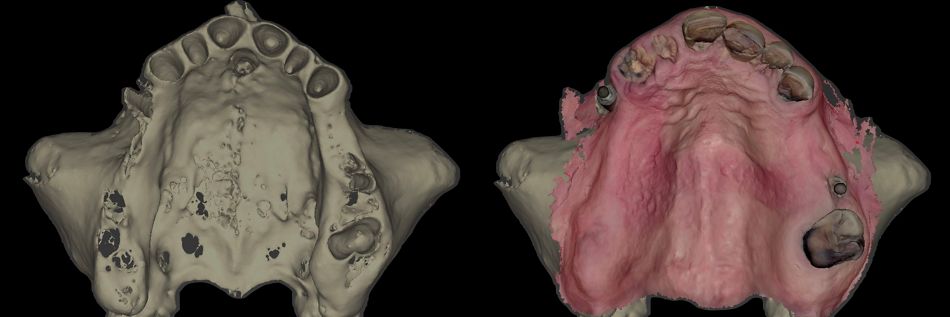

1.    Data Acquisition: Initial scan of the upper jaw as the starting point (Figs. 9,10) along with intraoral and extraoral pictures.

• Segmentation of the bone using AI and superimposition of the intraoral scan file (Fig. 12).

Printed models were fabricated from intraoral scans, and the final upper and lower removable prostheses with a resin and metal framework were prepared in advance, prior to the extraction of the remaining teeth and removal of failed old implants (Figs. 59,60).